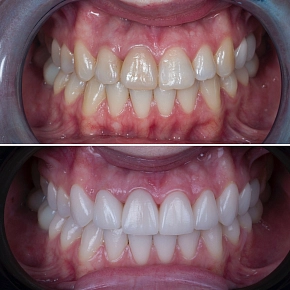

Успешное ортодонтическое лечение